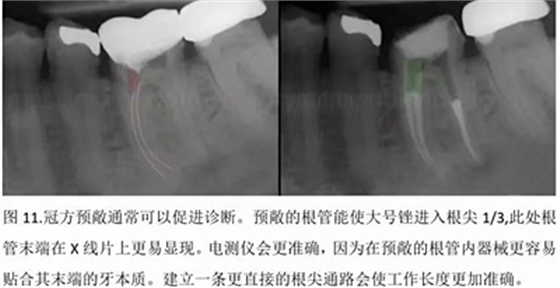

本文的目的是描述一種旨在優(yōu)化根管根尖部分預備的預敞技術(shù)。根管頸部或冠方的早期預敞對于減少初尖銼直徑和根尖部根管直徑之間的差異至關(guān)重要。大量研究表明,手用或機用器械預敞根管能顯著減少器械折斷的發(fā)生率。